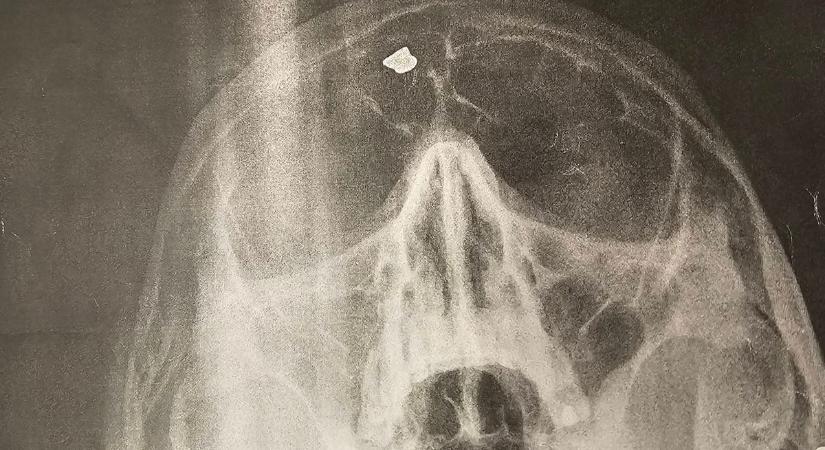

Amit a beteg fejében találtak, az mindenkit lesokkolt, de a gyöngyösi orvos követői ezt is űberelték

Hihetetlen, milyen őrültségekre képesek a gyerekek játékból.